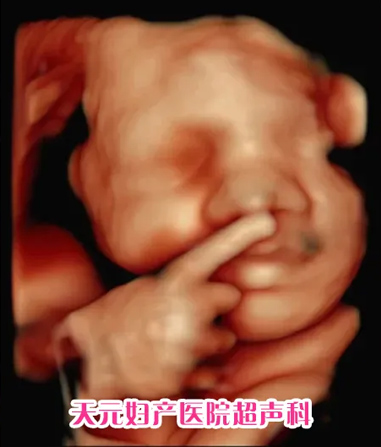

美国GE-E10四维彩超成熟的煊光、煊影、煊流成像技术,通过细致的多切面成像分析胎儿的解剖结构及发育状况,能够提供更多、更准确的图像数据,可以更加清晰、完整地记录胎儿宫内的高清动态。提供了卓越的图像品质及完整的专业妇产超声临床解决方案。